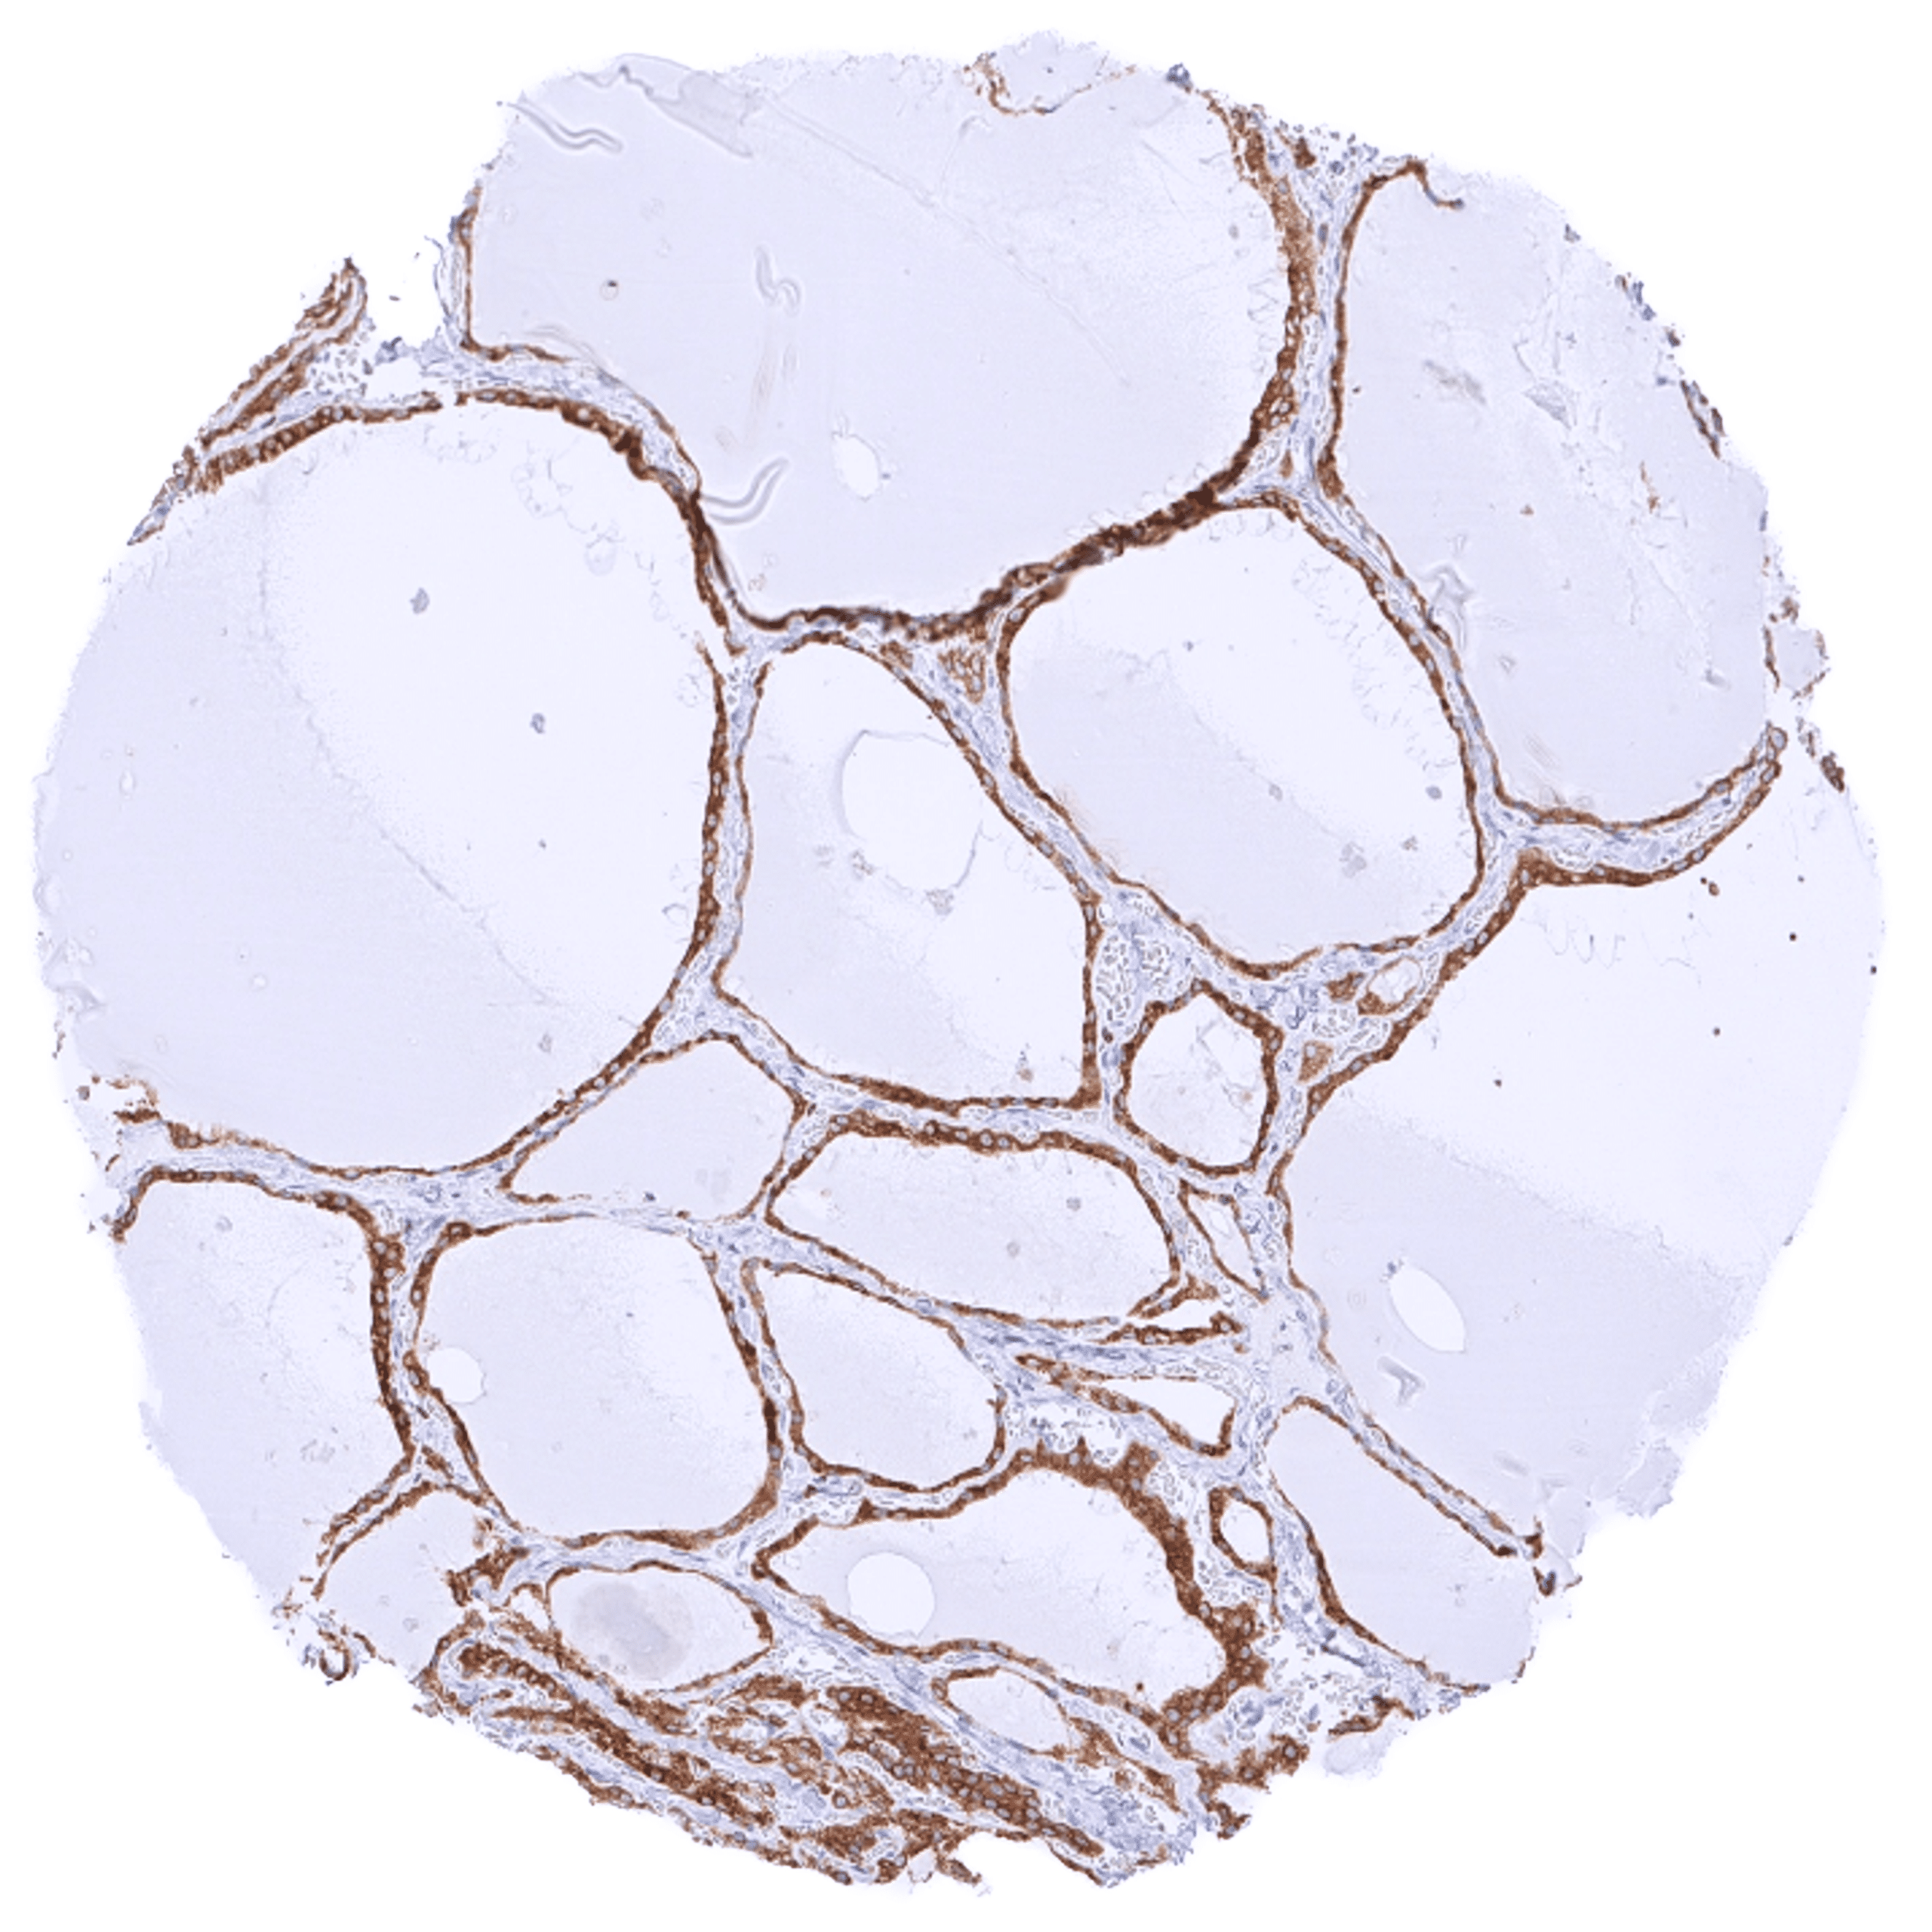

| Endocrine Tissues | Thyroid | Strong cytoplasmic bcl-2 staining of follicular cells. |